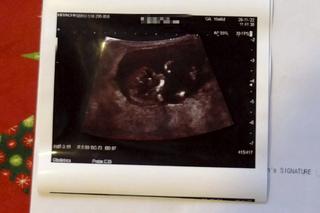

- W naszej sytuacji mogą znaleźć się inne pary, którym nie zdoła pomóc dr Suleiman... Prawda jest taka, że mogło dojść do aborcji żywego dziecka, w szpitalu, zgodnie z prawem - mówi mężczyzna. Ostatnie badania pokazują, że dziecko rozwija się dobrze i zgodnie z planem ma przyjść na świat w czerwcu.